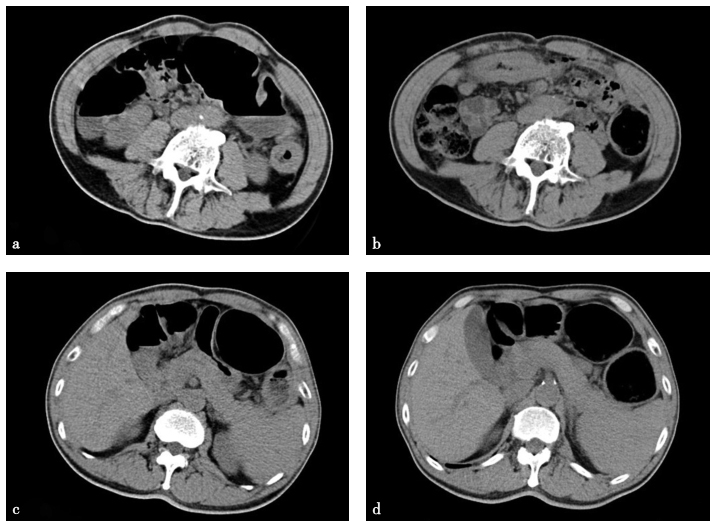

2016年12月9日和2017年1月12日两次CT比较见图1。

图1CT检查

a、c. 2016年12月9日;b、d. 2017年1月12日

血常规、肝肾功能、粪便常规+隐血正常;尿常规蛋白(+)。腹部立位X线平片示肠腔积气。肠系膜血管超声未见异常。腹盆CTA示腹主动脉及其分支未见明显管腔狭窄,结肠肠壁未见增厚。结肠镜示全结肠肠腔宽大,结肠脾曲、降结肠、乙状结肠肠腔未见狭窄,结肠黑变病。胃肠动力检查:48h胃肠通过试验(gastrointestinal transit test,GITT),排出15%,直肠乙状结肠以上55%,直肠乙状结肠以下30%;肛门直肠压力测定未见明显异常。